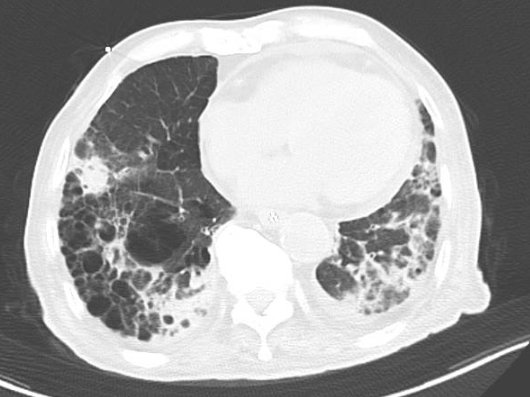

近日,潍坊市人民医院老年医学科接诊一例高龄患者,因饮食不佳5天来诊,无发热,偶有咳嗽咳痰,无恶心呕吐,无胸痛,在外未予治疗。双肺可闻及湿性啰音,余无明显异常。完善相关辅助检查,血常规及肺部ct结果提示肺炎。

图2 肺部ct